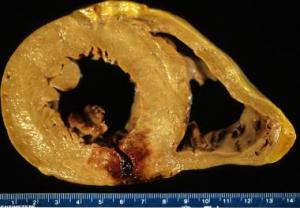

Myocardial infarction (MI) (ie, heart attack) is the irreversible death (necrosis) of heart muscle secondary to prolonged lack of oxygen supply (ischemia).